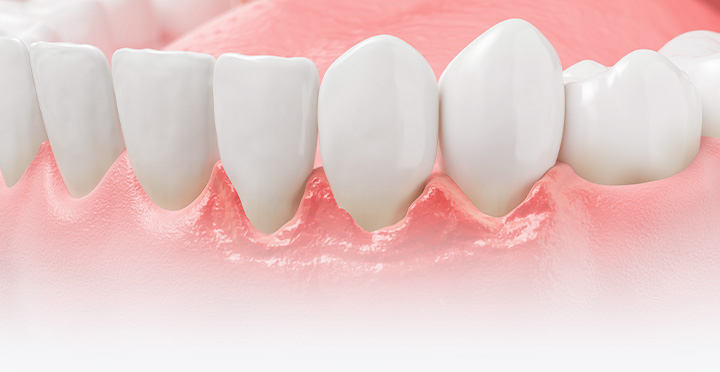

붓고 피나는 잇몸병의 주된 원인은,

바로 치태와 치석입니다.

치태

치석의 전 단계로, 치아 표면에 세균이 특정한 타액과

만나서 생긴 끈끈하고 투명한 세균막입니다.

치석

치아 표면에 있는 세균막이 각종 타액과 함께 침착되어

만들어진 것으로 세균과 무기질로 이루어진 딱딱한

세균 덩어리이며, 치주 질병의 주요 원인입니다.

소리 없이 진행되는 풍치는 치아를 상실하는

가장 큰 원인이므로

조기 발견, 치료가 중요합니다!